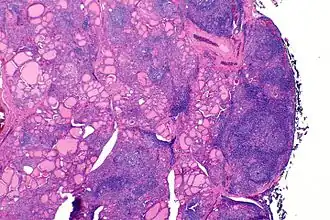

Physiopathologie et anatomopathologie

Sur le plan physiopathologique, les anticorps dirigés contre la thyroperoxydase et/ou la thyroglobuline causent une destruction progressive des follicules thyroïdiens de la glande thyroïde.

Macroscopiquement, le goitre est symétrique, non adhérent aux éléments péri-thyroïdiens et présente une surface capsulaire discrètement bosselée[1].

En microscopie les lésions consistent en une association de fibrose interstitielle, d'infiltration lymphoïde et de destruction épithéliale[1],[2]. Le degré de fibrose est très variable[1]. L'infiltration lymphoïde présente une organisation en follicules avec des lymphocytes B au centre et des lymphocytes T dans le cortex[2]. Les cellules épithéliales thyroïdiennes sont également modifiées, apparaissant élargies et acidophiles (cellules de Hürthle)[2].